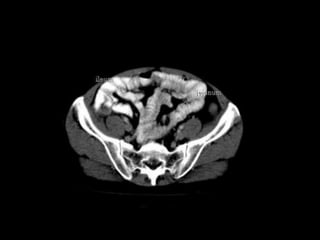

Right and LeftInframesocolic Spaces The right and left inframesocolic spaces are separated from the supramesocolic spaces by the transverse mesocolon and from the paracolic gutters laterally by the ascending or descending colon.The smaller right inframesocolic space is limited inferiorly by the attachment of the small bowel mesentery to the cecum; collections in this space generally do not extend into the pelvis However, the larger left inframesocolic space communicates freely with the pelvis. Peritoneal spaces